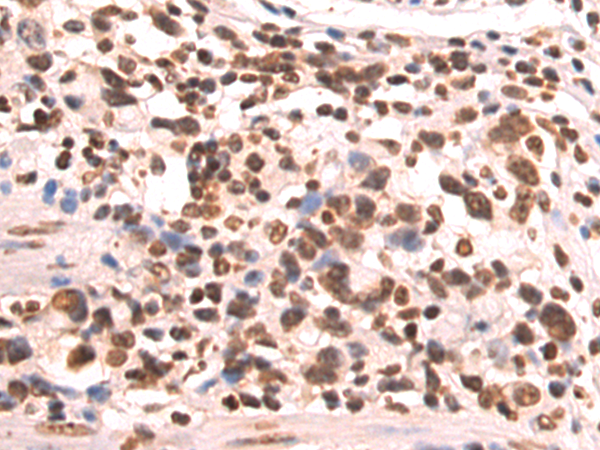

分类: 科研抗体货号: P12820别名: CENF; hcp-1; CILD31; PRO1779应用: IHC反应种属: Human